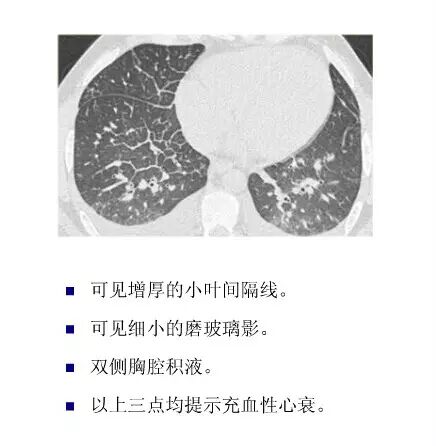

平片如何看心衰